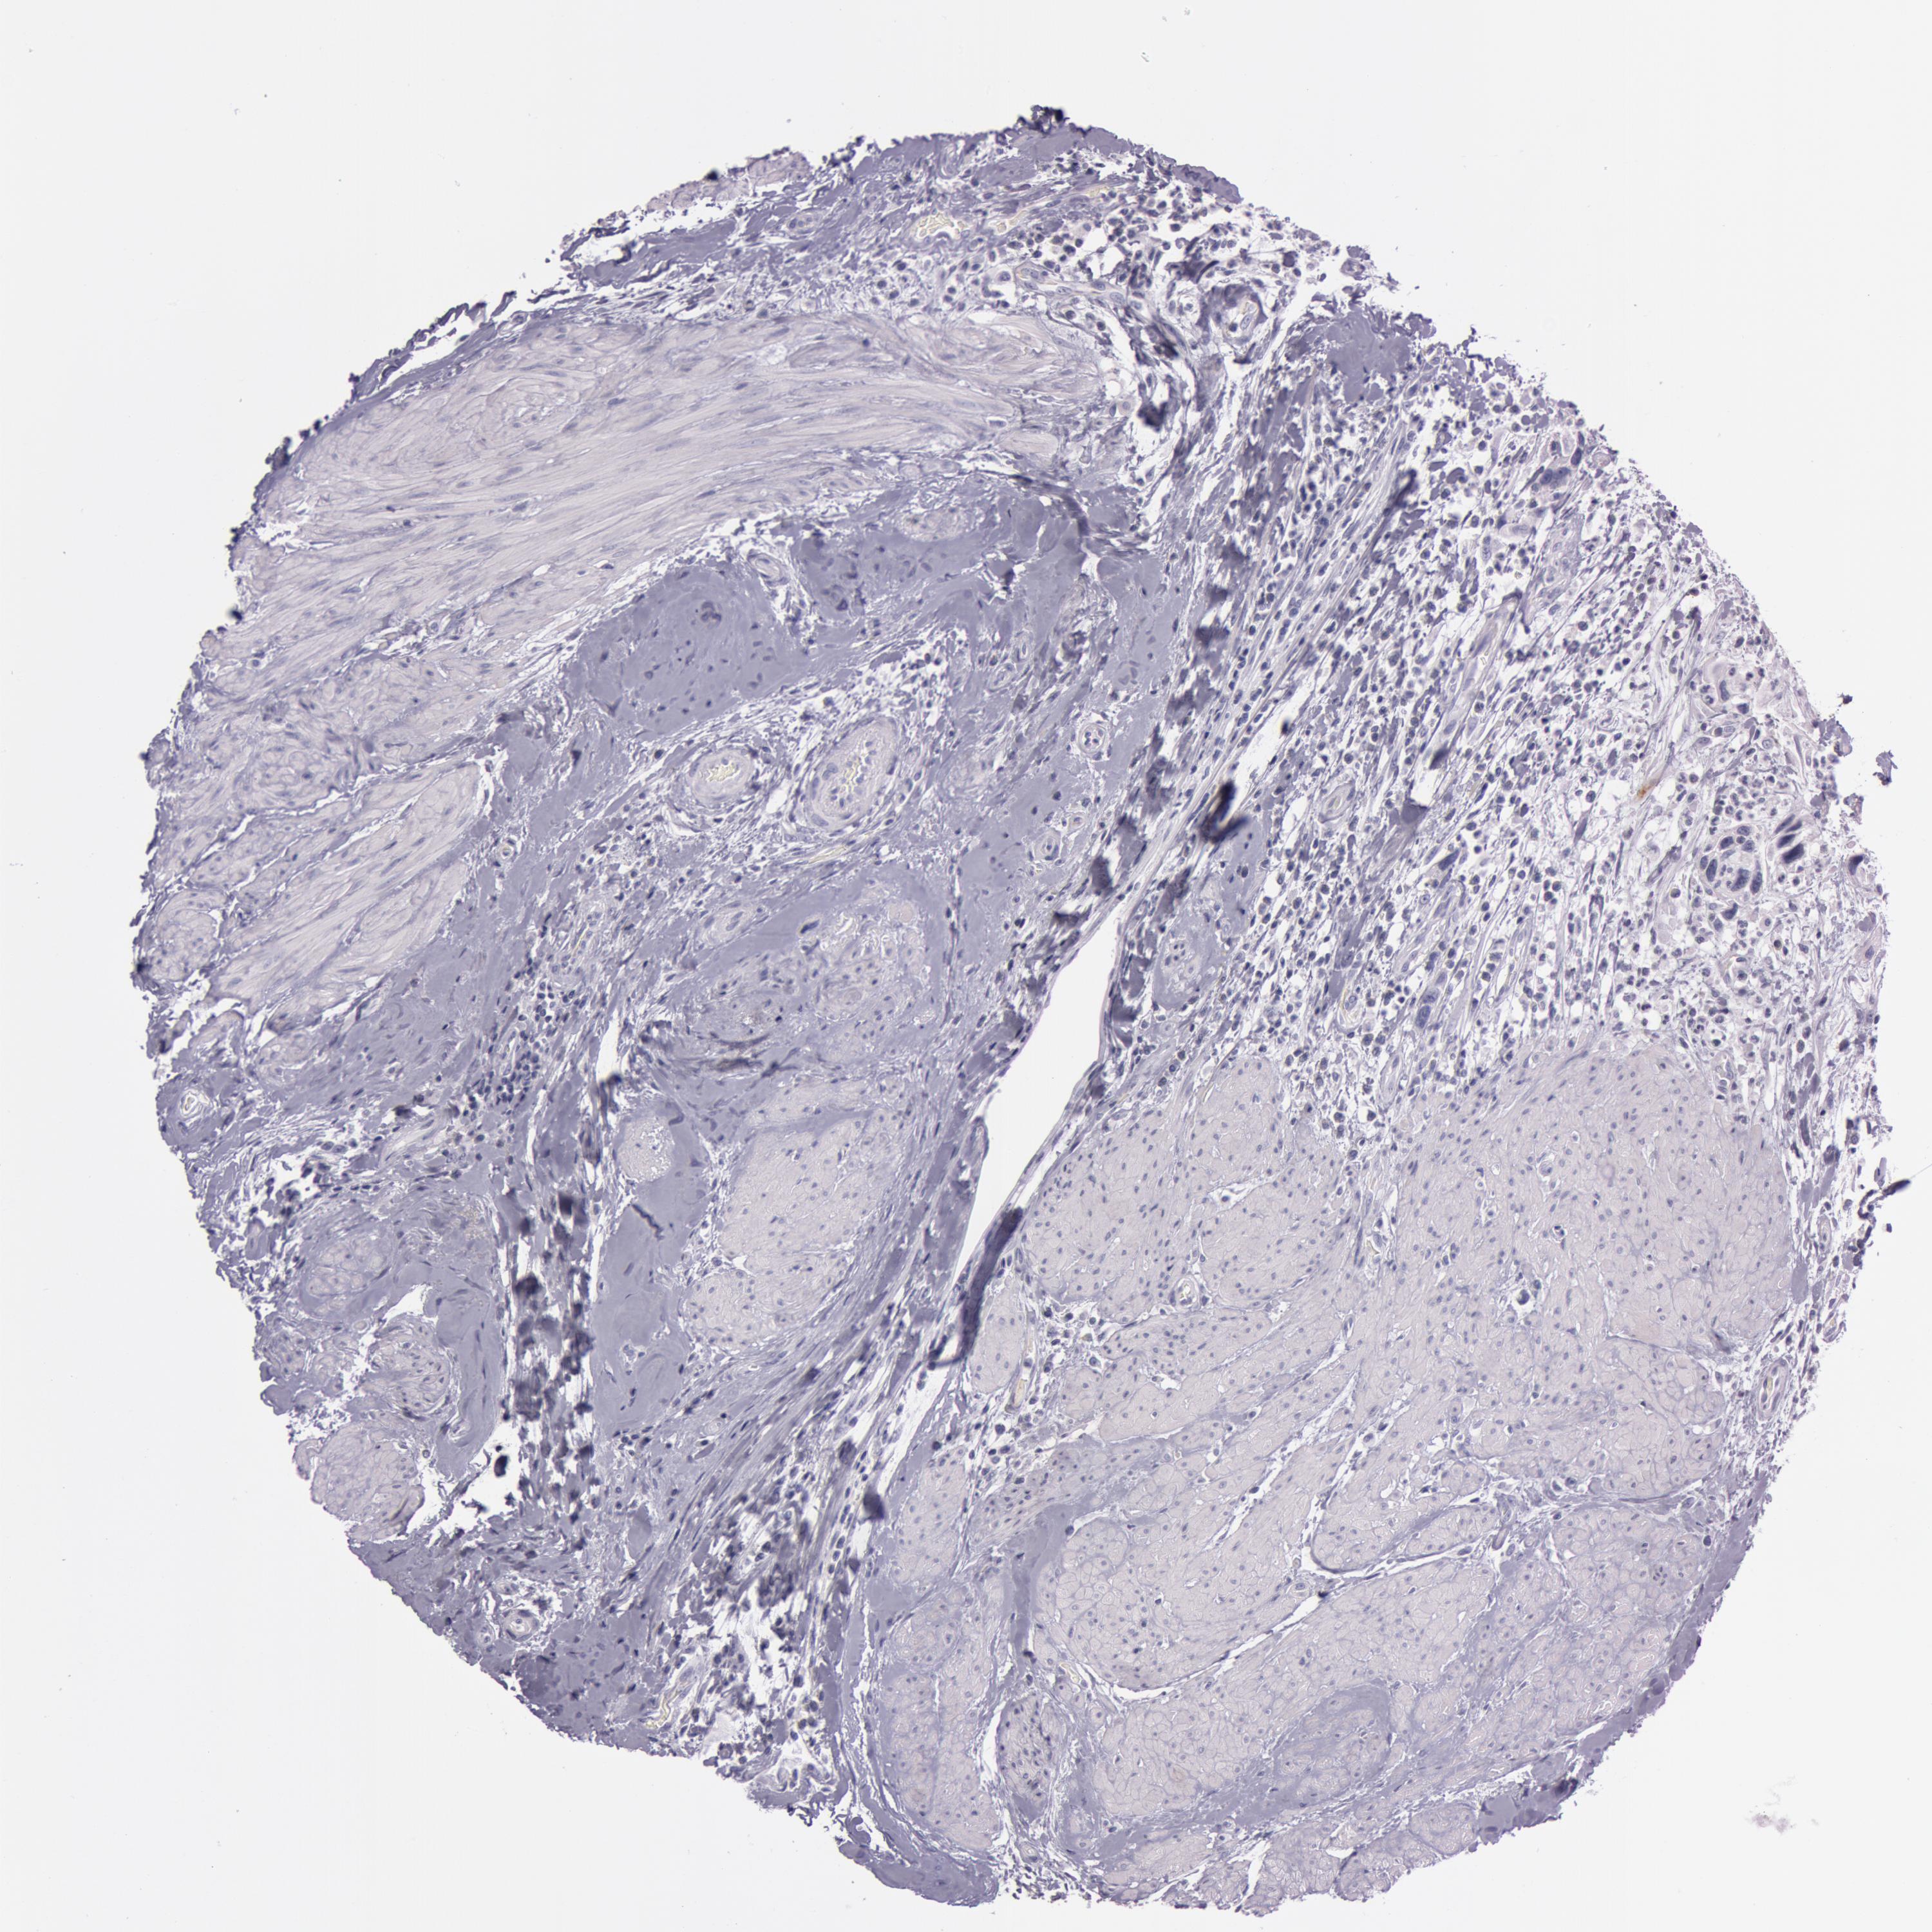

UROTHELIAL CANCER - Protein expressioni

A mouse-over function shows sample information and annotation data. Click on an image to view it in a full screen mode. Samples can be filtered based on level of antibody staining by selecting one or several of the following categories: high, medium, low and not detected. The assay and annotation is described here.

Note that samples used for immunohistochemistry by the Human Protein Atlas do not correspond to samples in the TCGA dataset.

Antibody stainingi

Antibody staining in the annotated cell types in the current human tissue is reported as not detected, low, medium, or high, based on conventional immunohistochemistry profiling in selected tissues. This score is based on the combination of the staining intensity and fraction of stained cells.

Each image is clickable and will lead to virtual microscopy that enables deeper exploration of all samples and also displays staining intensity scores, fraction scores and subcellular localization as well as patient and tissue information for each sample.

Antibody HPA010593

Antibody CAB001451

Urothelial carcinoma, Low grade

Urothelial carcinoma, High grade

Adenocarcinoma, NOS